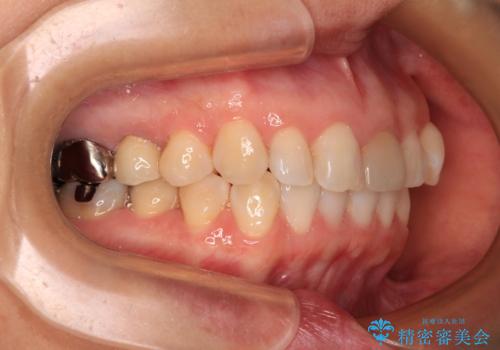

気になる下顎歯列のみをインビザラインで部分矯正

- 上下前歯のデコボコを気にして来院された患者様です。

カウンセリングにて詳しく話を聞いたところ、一番気になっているのは下顎前歯の叢生であり、上顎犬歯はあまり気になっていないとのことでした。

矯正治療は、歯の後戻りを抑制するために、治療終了後も保定装置をしっかりと使用していただくことが必須であるため、気になっている下顎だけを整えることで、その負担を半減できると考え、下顎のみの部分矯正として治療を行うこととしました。

装置としては、叢生の程度が強くなかったため、インビザラインの廉価版であるモデレート・パッケージを使用することとしました。

当院では治療前の歯列が整っていない限り、下顎前歯の舌側をワイヤーで固定するようにしています。下顎のみの部分矯正としたことで、マウスピース保定の負担を軽減することができました。

上顎は、失活して歯の色が変色しているため、将来的に補綴治療で自然な口元に仕上げていきたいとのことでした。